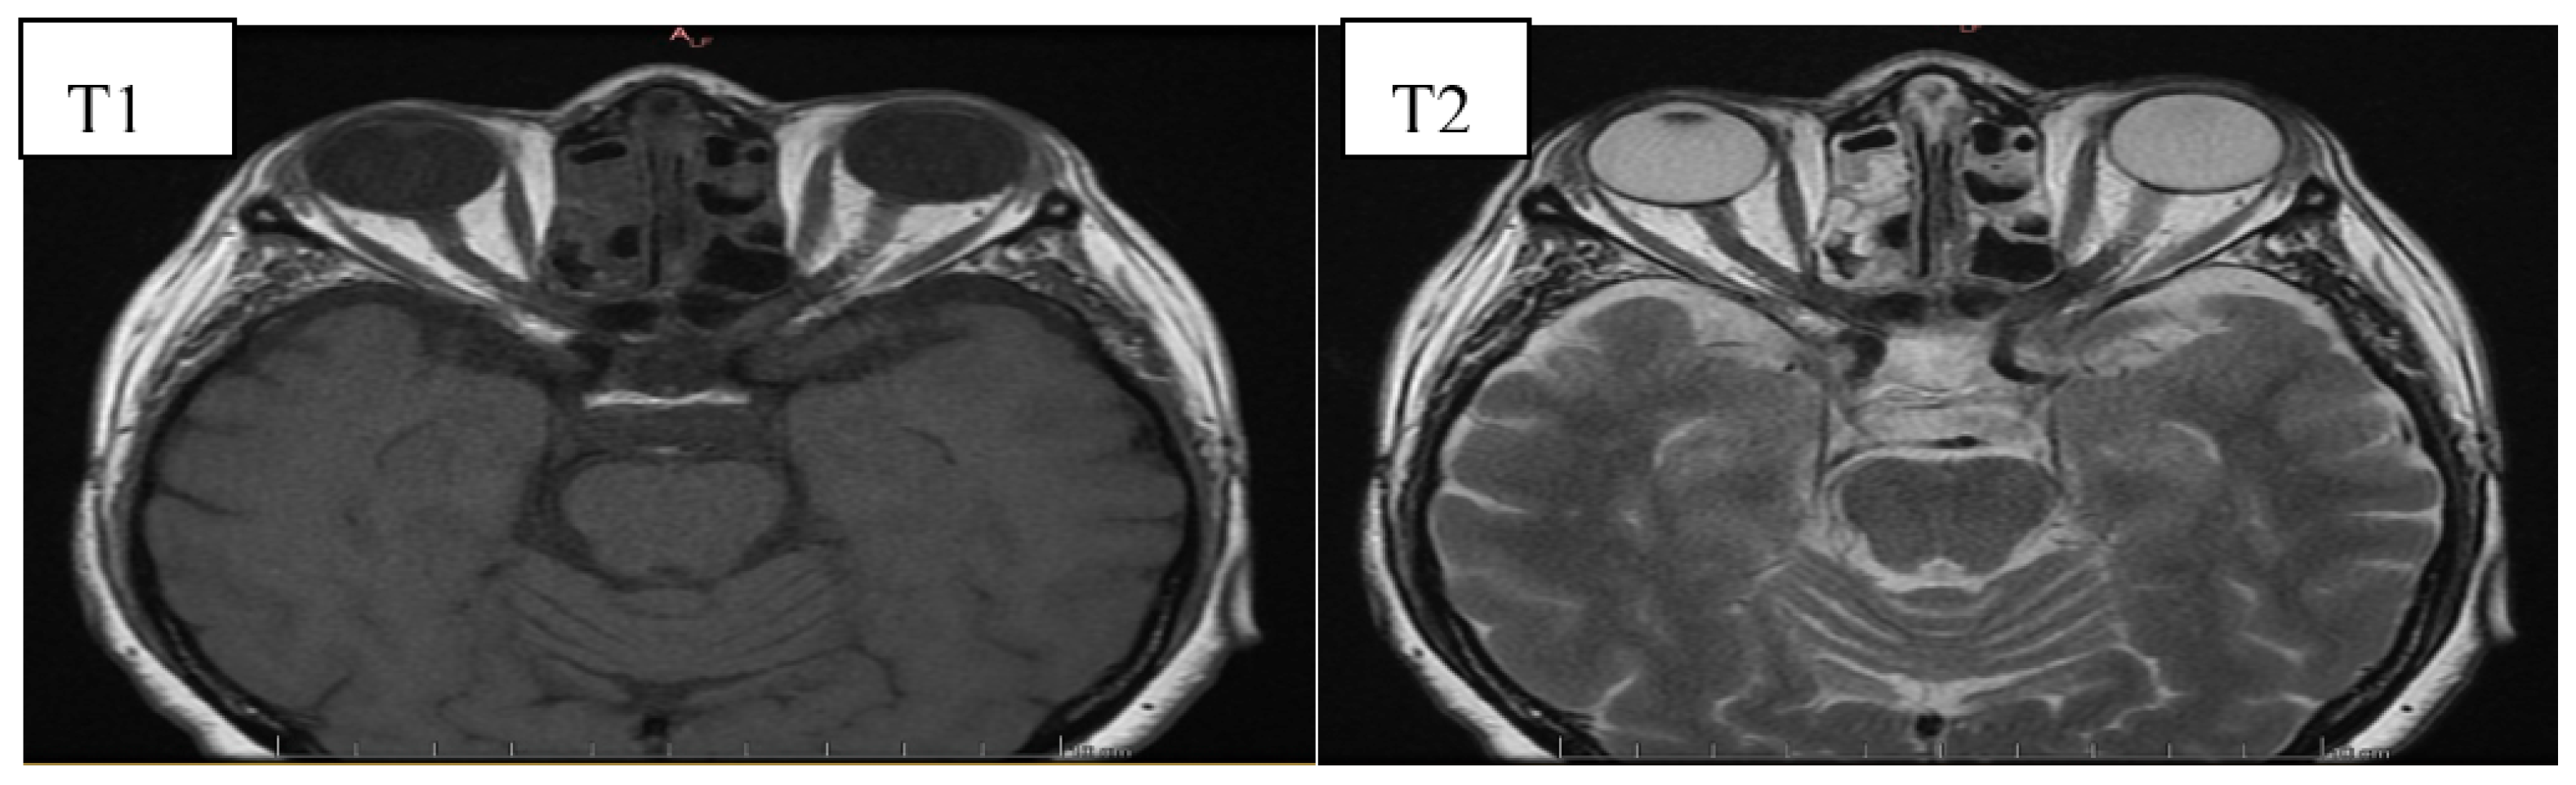

6. Image Evaluation

- Gonçalves, A.C.P.; Gebrim, E.M.M.S.; Monteiro, M.L.R. Imaging studies for diagnosing Graves’ orbitopathy and dysthyroid optic neuropathy. Clinics 2012, 67, 1327–1334. [Google Scholar] [CrossRef]

- Kahaly, G.J. Imaging in thyroid-associated orbitopathy. Eur. J. Endocrinol. 2001, 145, 107–118. [Google Scholar] [CrossRef]

- Müller-Forell, W.; Kahaly, G.J. Neuroimaging of Graves’ orbitopathy. Best Pract. Res. Clin. Endocrinol. Metab. 2012, 26, 259–271. [Google Scholar] [CrossRef] [PubMed]

- Cakirer, S.; Cakirer, D.; Basak, M.; Durmaz, S.; Altuntas, Y.; Yigit, U. Evaluation of extraocular muscles in the edematous phase of Graves ophthalmopathy on contrast-enhanced fat-suppressed magnetic resonance imaging. J. Comput. Assist. Tomogr. 2004, 28, 80–86. [Google Scholar] [CrossRef]